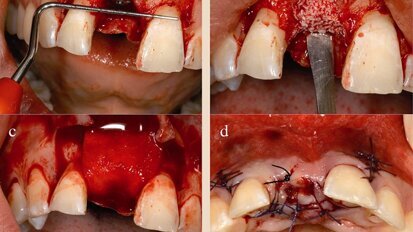

Neoss photos

Neoss Implantat System